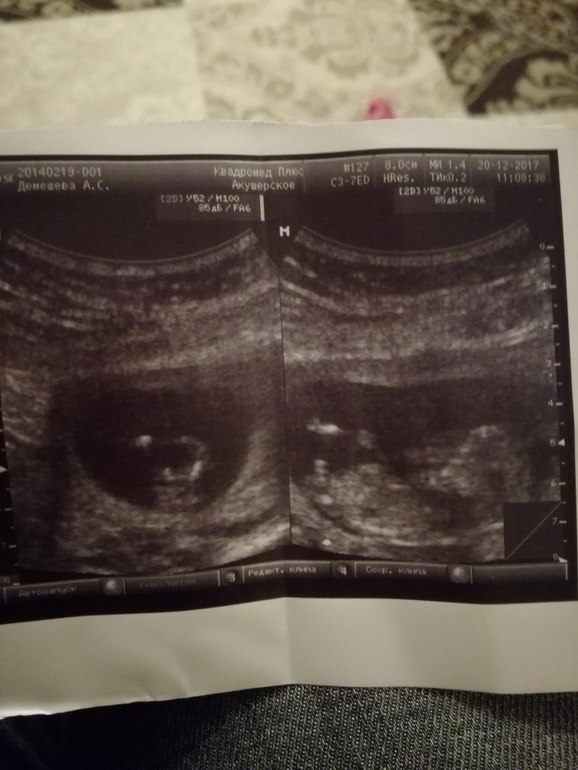

Ох как я ждала этот день, по узи всё хорошо кровь будет через 2 дня. По сроку поставили 12 и 4 ( по месячным 11,5 ) но я думаю что была очень ранняя О так как я делала тесты с 11 дц и они были пустые. . КТР 60 ЧСС 159. Предположили мальчика, узист знатный по Подольску ( Неплохов А.Ю.) ну и фото прилагаю. Сына очень хочу, это просто моя мечта, но настроена опять на девку. Мальчик для меня это просто чудо какое то и что то из ряда фантастики. Посмотрите фото, может кто поможет определить пол.. Первое фото профиль, второе вид снизу на попку. Фотки он как то странно распечатал, 2 фото на одной бумаги так что качество не очень.

На фото в профиль ооооочень даже мальчик, мне тоже такой торчун в эту беременность показали и тоже мальчик, узистка сказала, на все 100%. Срок по м 11 и 5 был, ктр 54 мм, у вас больше, так что я в вашем мальчике уверена. Дай Бог😘

На счёт пола не скажу, снизу не видно мужчинку, сбоку размыто как то. А я наоборот очень хочу дочь 🙈 Это же такая нежность! Боюсь как бы на 2 скрининге не выросло чего 😰